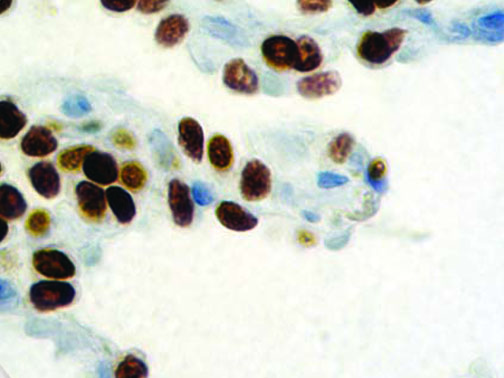

It is the ICU physician who is most likely to witness one of the deadliest manifestations of the abnormal immunological response, the cytokine storm syndrome (CSS). This response is also referred to by some as the cytokine release syndrome (CRS). CSS is characterized by continuous activation and expansion of macrophage and lymphocyte populations, which secrete large amounts of cytokines, causing the cytokine storm. This massive cytokine release is akin to hemophagocytic lymphohistiocytosis (HLH) disease, a syndrome characterized by initial unchecked and persistent activation of cytotoxic T lymphocytes and NK cells.

Clinical and laboratory manifestations of HLH include fever, enlarged liver and/or spleen, neurologic dysfunction, coagulopathy, liver dysfunction, cytopenias (i.e., low levels of erythrocytes, leukocytes, and/or platelets), hypertriglyceridemia, hyperferritinemia, hemophagocytosis, and eventually diminished NK cell activity as the immune system becomes progressively paralyzed. HLH can be familial (primary HLH) or secondary to another disease process (sHLH), such as rheumatic disease, in which it is referred to as macrophage activation syndrome (MAS, characterized by elevated ferritin).